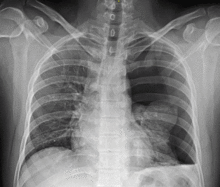

Chest X-ray

Traditionally a plain radiograph of the chest, ideally with the X-ray beams being projected from the back (posteroanterior, or "PA"), has been the most appropriate first investigation. These are usually performed during maximal inspiration (holding one's breath); no added information is gathered by obtaining a chest X-ray in expiration (after exhaling).[12][13] If the PA X-ray does not show a pneumothorax but there is a strong suspicion of one, lateral X-rays (with beams projecting from the side) may be performed, but this is not routine practice.[13][17] It is not unusual for the mediastinum (the structure between the lungs that contains the heart, great blood vessels and large airways) to be shifted away from the affected lung due to the pressure differences. This is not equivalent to a tension pneumothorax, which is determined mainly by the constellation of symptoms, hypoxia, and shock.[12]

The size of the pneumothorax (i.e. the volume of air in the pleural space) can be determined with a reasonable degree of accuracy by measuring the distance between the chest wall and the lung. This is relevant to treatment, as smaller pneumothoraces may be managed differently. An air rim of 2 cm means that the pneumothorax occupies about 50% of the hemithorax.[13] British professional guidelines have traditionally stated that the measurement should be performed at the level of the hilum (where blood vessels and airways enter the lung) with 2 cm as the cutoff,[13] while American guidelines state that the measurement should be done at the apex (top) of the lung with 3 cm differentiating between a "small" and a "large" pneumothorax.[23] The latter method may overestimate the size of a pneumothorax if it is located mainly at the apex, which is a common occurrence.[13] The various methods correlate poorly, but are the best easily available ways of estimating pneumothorax size.[13][17] CT scanning (see below) can provide a more accurate determination of the size of the pneumothorax, but its routine use in this setting is not recommended.[23]